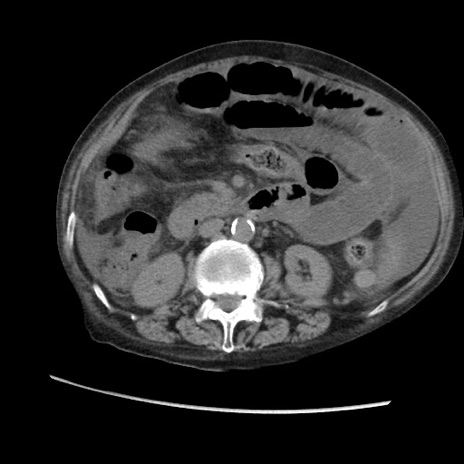

症例31(横断像)

【症例】80歳代 女性

【主訴】腹部膨満感

【現病歴】他院にて肝硬変にてフォロー中。1週間前から便秘、腹部膨満感、臍部腫瘤あり受診となる。

【既往歴】肝硬変

【身体所見】腹部膨隆あり、皮膚変化なし、疼痛なし。

【データ】WBC 4600、CRP 0.25